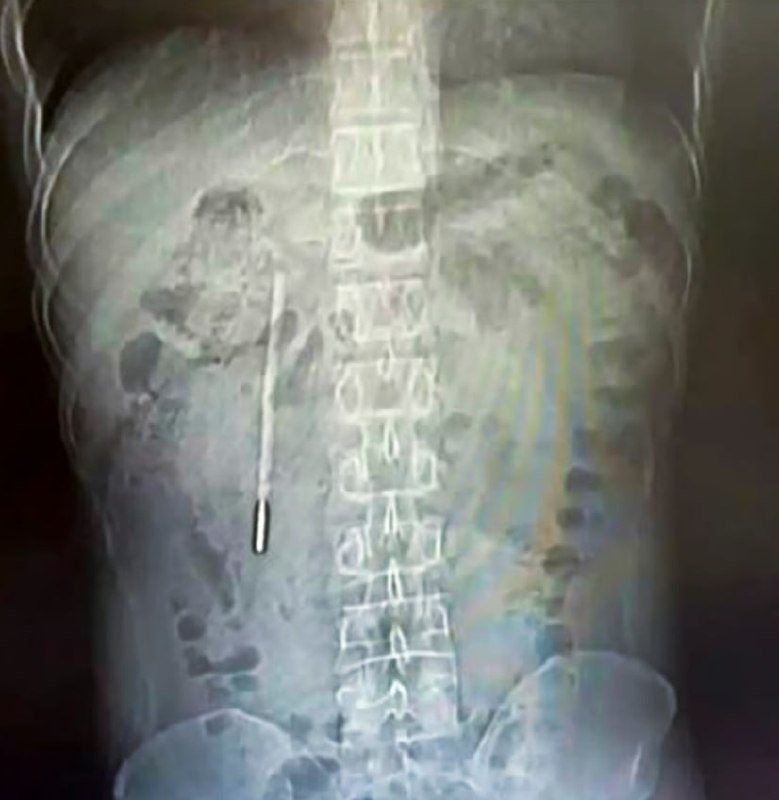

20 il əvvəl termometr udmuşdu, indi çıxarıldı

ŞOK HADİSƏ: 20 il əvvəl udduğu termometr bağırsağından ÇIXDI – FOTO